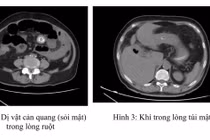

Tại đây, qua thăm khám kỹ lưỡng và thực hiện các cận lâm sàng chuyên sâu như chụp CT-scan bụng, kết quả cho thấy bệnh nhân có nhiều sỏi đường mật trong gan trái và sỏi túi mật, cùng với đó là gan trái bị xơ teo nhỏ.

Dựa trên các kết quả chẩn đoán hình ảnh, bác sĩ nhận định sỏi đã hình thành lâu trong ống mật chủ dẫn đến tắc mật, đồng thời ống gan trái bị chít hẹp khiến cho toàn bộ thùy gan trái của bệnh nhân đã bị xơ teo và tạo các túi sỏi.